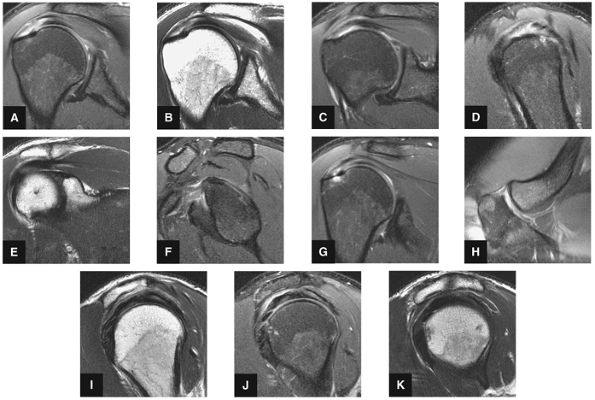

FIGURE 8.29 ● (A) Coronal T1- or PD-weighted images are used to evaluate the distal acromion. (B) Coronal FS PD-weighted images show the majority of the cranial-to-caudal extent of the subscapularis tendon. This image is used to triangulate on subscapularis tears suspected on other planes. Most commonly, tears of the subscapularis begin in the superior articular margin of the tendon. (C) In the setting of supraspinatus tears, coronal T1- or PD-weighted images at or near this image slice are best for assessment of supraspinatus atrophy. (D) Coronal FS PD-weighted images display two important anatomic structures. The first is the anterior-most portion of the distal supraspinatus tendon (also called the “anterior leading edge”), which is seen attaching at the greater tuberosity. This location is the most common starting point for tears of the supraspinatus tendon. The second is the LHBT as it turns 90° around the lesser tuberosity within the proximal portion of the bicipital groove. This is a common location for tendinosis of the biceps tendon. In addition, medial subluxation is visualized in this location, not uncommonly associated with tears of the distal superior supraspinatus tendon. (E) Coronal T1- or PD-weighted images are used to depict the undersurface spurring of the acromion and lateral downsloping of the acromion, both of which are associated with impingement. (F) Coronal FS PD-weighted images show the superior labrum (the anterior superior quadrant). Areas of linear increased signal are normal at this image location, due to fluid/synovium interposed between the multitude of structures coursing toward the superior labrum, including the biceps tendon and the superior glenohumeral ligament. Linear high signal visualized in the labrum is more likely to be due to a tear anterior or posterior to the 12-o—clock position on the glenoid. (I) Coronal T1- or PD-weighted images display the Hill-Sachs lesion, which is visualized as flattening and impaction of the posterior lateral humeral head. This lesion should be differentiated from the extremely common presence of subcortical cystic changes in the posterior lateral humeral head. (J) Coronal FS PD-weighted images are used to display subacromial/subdeltoid fluid. Even in the absence of a rotator cuff tear, fluid in the subacromial/subdeltoid tendon should be described because subacromial/subdeltoid bursitis may mimic the symptoms of a rotator cuff tear and can be a secondary sign of impingement. (K) Coronal T1- or PD-weighted images are used for assessment of infraspinatus muscle atrophy in the setting of rotator cuff tears. This coronal image location is preferred over sagittal plane images because medial retraction of the infraspinatus muscle from a tendon tear can appear falsely atrophic on sagittal images. (L) Coronal FS PD-weighted images demonstrate the insertion of the infraspinatus tendon on the posterior superior portion of the humeral head. Because the insertion is oblique, small tears of the infraspinatus can be difficult to assess in the coronal plane, and infraspinatus pathology in the coronal plane is cross-referenced with sagittal images.

FIGURE 8.30 ● Axial images through the AC joint should be obtained on all shoulder MR examinations. (A) Axial T1- or PD-weighted images at this location are used to identify fractures of the distal clavicle and to demonstrate an os acromiale. (B) Axial FS PD-weighted images show cartilage covering the distal aspect of the clavicle and the medial aspect of the acromion at the AC joint. Cartilage defects and thinning, as well as subchondral bone marrow edema and cystic change, are evaluated on axial images through the AC joint. These degenerative changes can mimic the symptoms of a rotator cuff tear. (C) Axial T1- or PD-weighted images demonstrate the Hill-Sachs lesion of the humeral head, usually visualized as focal flattening or concave deformities in the posterolateral humeral head. The Hill-Sachs lesions is identified on the first or second superior axial image through the humeral head. Subcortical cystic change is more commonly visualized in the posterolateral humeral head and is usually an incidental finding in asymptomatic patients. (D) Axial FS PD-weighted images depict the biceps tendon coursing across the anteromedial aspect of the humeral head, within the rotator interval. This image location serves as a starting point for following the remainder of the biceps tendon into the bicipital groove on successive axial images moving from cranial to caudal. Tears of the supraspinatus and infraspinatus tendons are also identified at this image location on axial images. (E) Axial T1- or PD-weighted images allow evaluation of subcoracoid impingement. (F) In this location, thickening and increased signal in the superior glenohumeral ligament and coracohumeral ligament on an axial FS PD-weighted image may indicate adhesive capsulitis, particularly when accompanied by thickening and increased signal within the inferior glenohumeral ligament. (G) Axial T1- or PD-weighted images are used to identify subcortical cystic change in the greater and lesser tuberosity. This finding is commonly an indirect indication of abnormality or tearing in the overlying distal supraspinatus and subscapularis tendons, respectively. (H) Axial FS PD-weighted images through the proximal bicipital groove are used to identify “hidden lesions,” which are diagnosed when the biceps tendon is medially subluxing out of the bicipital groove, usually into a distal subscapularis tear or anterior to the lesser tuberosity. A degenerated biceps tendon may appear flattened and elongated as it rounds the lesser tuberosity into the proximal bicipital groove. Commonly, only the medial “tail” of the flattened degenerated biceps tendon subluxes out of the groove; the remainder of the flattened biceps tendon stays within the groove. (I) Axial T1- or PD-weighted images display the osseous glenoid subchondral surface, which should appear flat. Osseous glenoid remodeling, hypertrophy, deformity, subchondral cystic change, and edema are commonly identified as indirect evidence of overlying chronic cartilage degeneration or prior trauma. Posterior glenoid spurring may completely replace a degenerated or markedly attenuated posterior labrum. (J) Axial FS PD-weighted images are optimal for displaying the glenoid and humeral head cartilage. Chondral fissures, thinning, and defects are visualized when viewing successive cranial-to-caudal images through the glenohumeral joint. The anterior and posterior labrum are also optimally visualized and are normally firmly adherent to the glenoid and glenoid articular cartilage. (K) Axial T1- or PD-weighted images are used to identify bony Bankart lesions. These lesions are seen on inferior axial images through the glenohumeral ligament as oblique fracture lines extending through the anterior inferior glenoid. (L) Axial FS PD-weighted images show the prominent anterior band of the IGHL, which is occasionally mistaken for a tear of the anterior inferior labrum when fluid is interposed between the anterior band and the normal labrum.